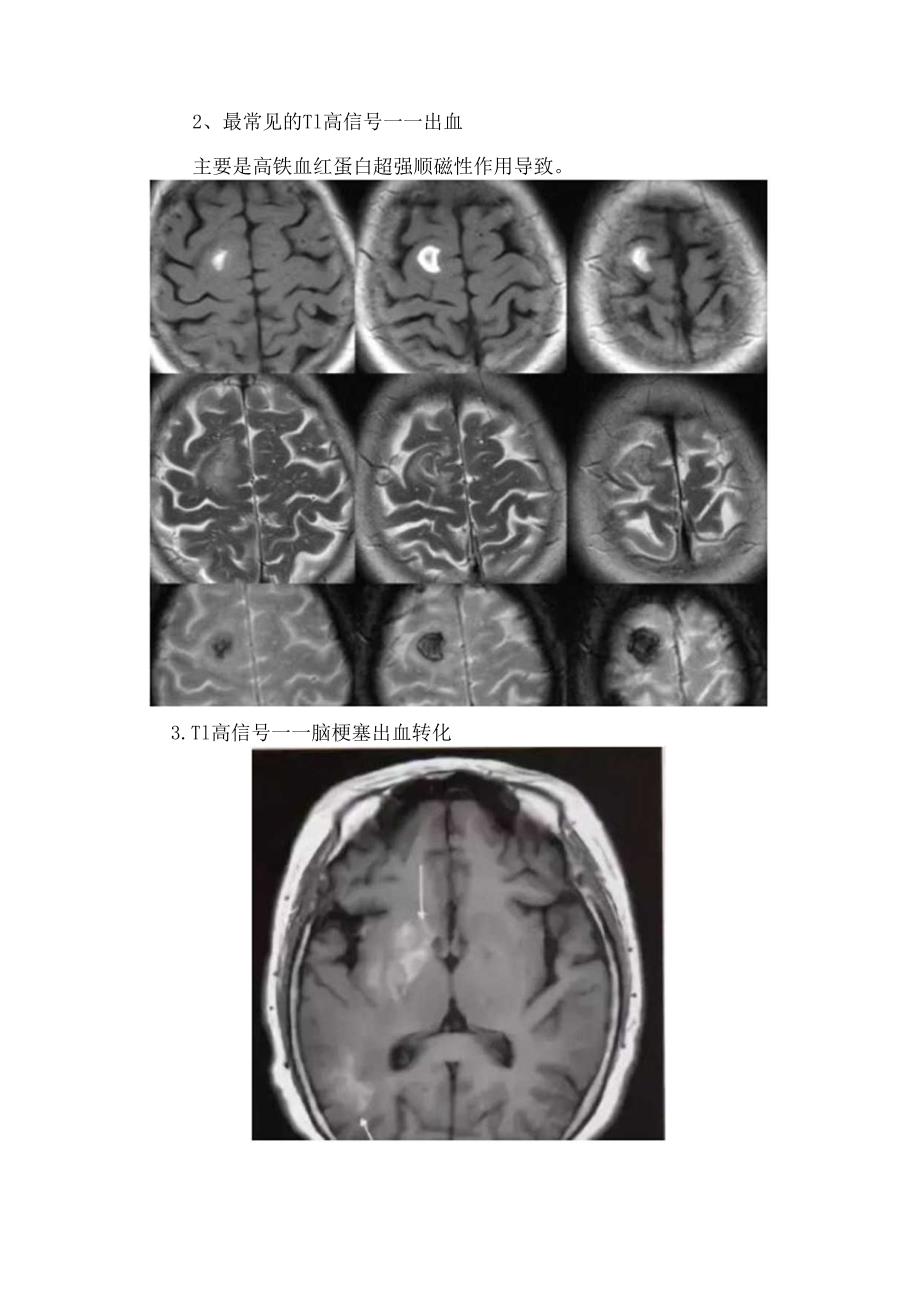

2、三为脂类分子。经典案例1.最常见的Tl高信号脂肪本例为肺胀体脂肪瘤。2、最常见的Tl高信号一一出血主要是高铁血红蛋白超强顺磁性作用导致。3.Tl高信号一一脑梗塞出血转化4. Tl高信号一一脑梗塞后皮层层状坏死坏死碎屑中的蛋白变性,或少量顺磁性物质沉积o5. Tl高信号动脉痛原因:慢血流造成的流动相关增强与血拴形成.7.Tl高信号动脉扩张迂曲8、TI高信号层面内血管在一定血流速度下,TlWI上呈高信号,由于TE明显延长,这些血管在T2WI呈流空信号。9. Tl高信号脑血管畸形脑血管畸形包括发育性静脉畸形、动静脉畸形、毛细血管扩张症、海绵状血管畸形。海绵状血管畸形常有慢性隐性出血,MRI为其首选影像学检查,典型表现为爆米花状高信号及病变周用含铁血黄素所致的信号环,但SWl比TIWl对出血更敏感。10. Tl高信号一一含蛋白物质下图为颅咽管瘤。下图为胶样囊肿。I1.Tl高信号一一肝性脑病镒过度沉积。黑色素的自由基含有不成对电子和氢质子的顺磁性效应。13.Tl高信号一一神经垂体抗利尿激素与血管加压素神经内分泌滤泡附近水分子弛豫增强。巨噬细胞吞噬脂质。15.Tl高信号钙化钙磁性钙盐+其他顺磁性物质;下图为软骨瘤。